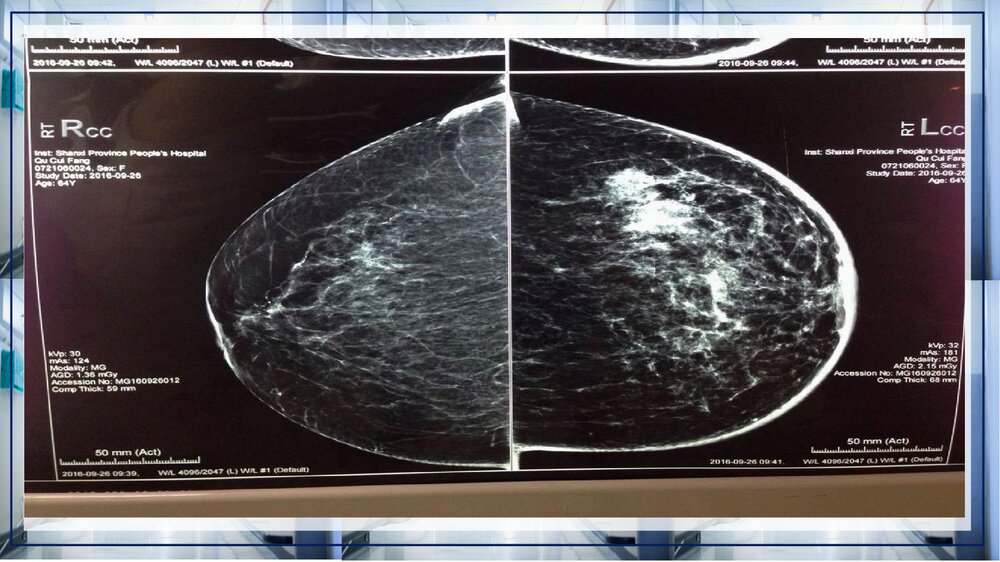

关于乳腺癌病例讨论关于乳腺癌病例讨论XXX:凡心20XX年X月XX日病史女性,52岁,发病急。发现左乳皮肤红肿2个月。患者入院前2月余,无意间发现左乳皮肤红肿,偶有乳房疼痛,门诊手诊可触及左乳外上片状增厚区,乳腺钼靶示左乳多发结节,BIRADS4b,右乳未见异常。既往史1998年因子宫肌瘤行子宫全切术;高血压病史17年,平素口服尼群地平、硝酸异山梨酯,自诉血压控制可;糖尿病病史15年,平素口服二甲双胍、格列本脲,自诉血糖控制可。专科检查双乳外形不对称,左乳明显增大,双乳头无内陷及偏移,左乳外上方可触及片状增厚区,范围约3.5*3㎝²,质硬,边界不清,活动度尚可,无压痛。左乳下方可见橘皮征,范围约20*22㎝,局部皮肤略红,皮温增高,右乳正常。左腋下可触及一肿大淋巴结,大小约1*1.5㎝²...